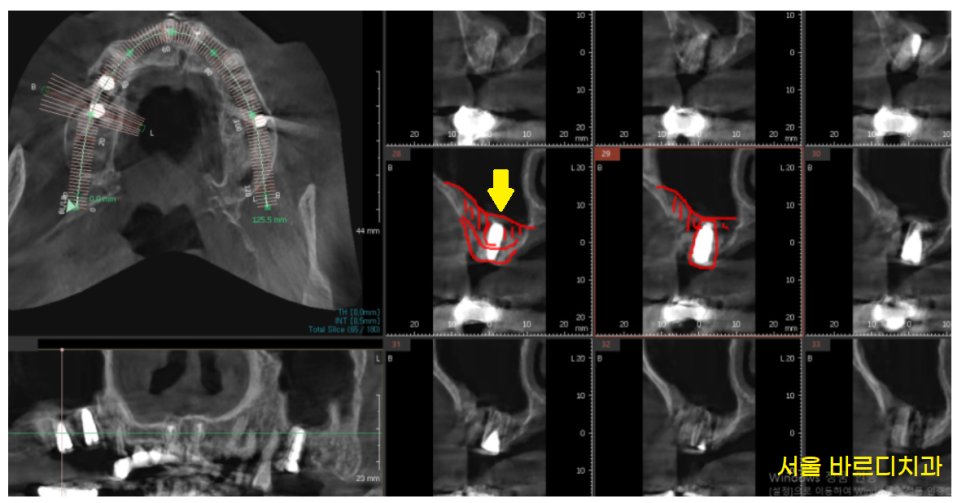

윗니 어금니의 경우

코 막을 들어올리는 상악동 거상술이 필요했기 때문입니다.

▼상악동거상술이란?▼

잠시 어려운 이야기를 해드리자면

위턱뼈는 해면골로 이루어져 있습니다.

타고나기를 뼈가 스펀지의 구멍처럼

뼈에 숭덩숭덩 구멍이 뚫려있다보니

약합니다.

23.06.21

23년 6월에 치료를 시작하시고

임플란트 치료 기간

얼마나 걸렸을까요?